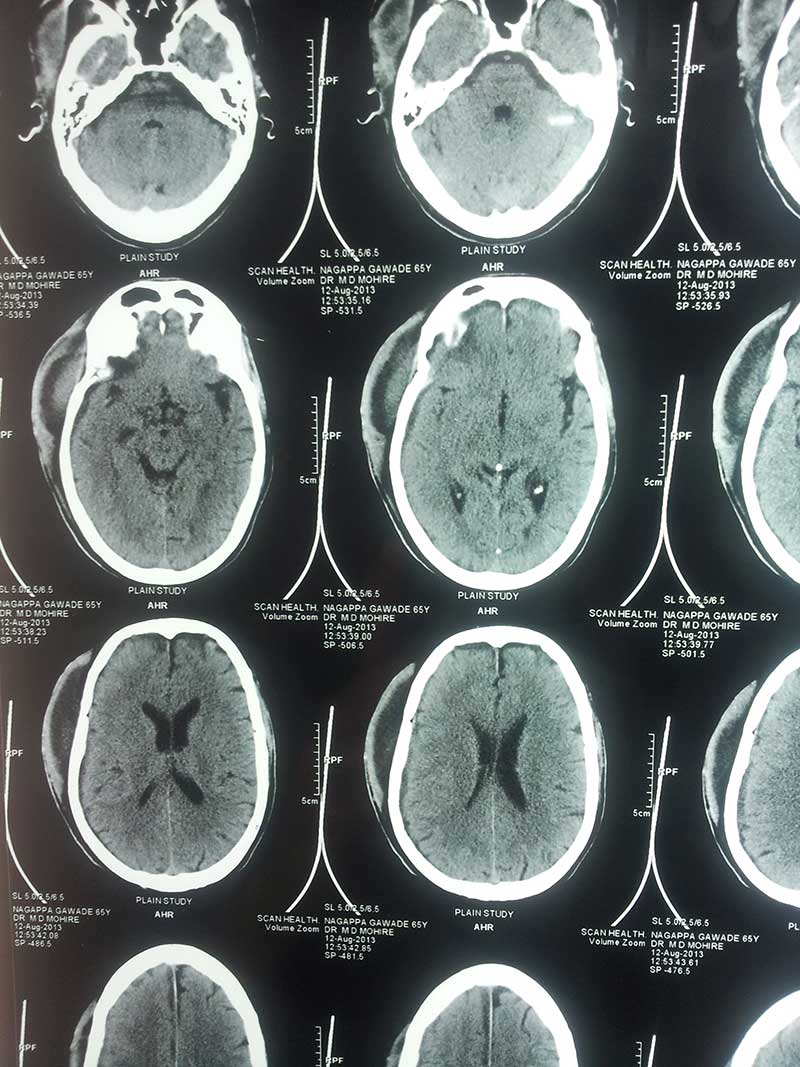

Brain Abscess Brain Abscess Post OP 2 Clinical Intra OP ,After Excising The Granuloma Intaop Scalp Abscess CT Scalp Abscess Cerebellar Abscess Post OP Clinical Cerebellar Abscess Brain TB Granuloma Post OP CT Scan Brain Infection Brain Abscess Preop MRI 2 Brain Abscess PRE OP Clinical 1 Brain Abscess PRE OP Brain Abscess Intraop 2 Brain Abscess Following Shunt Temporal Abscess T2W of TB Granuloma Scalp Abscess Preop CT Marking PRW OP MRI of TB Granuloma Post OP Clinical Photo Post OP Cerebellar Abscess Post OP Brain Abscess Intraop Specimen of Granuloma